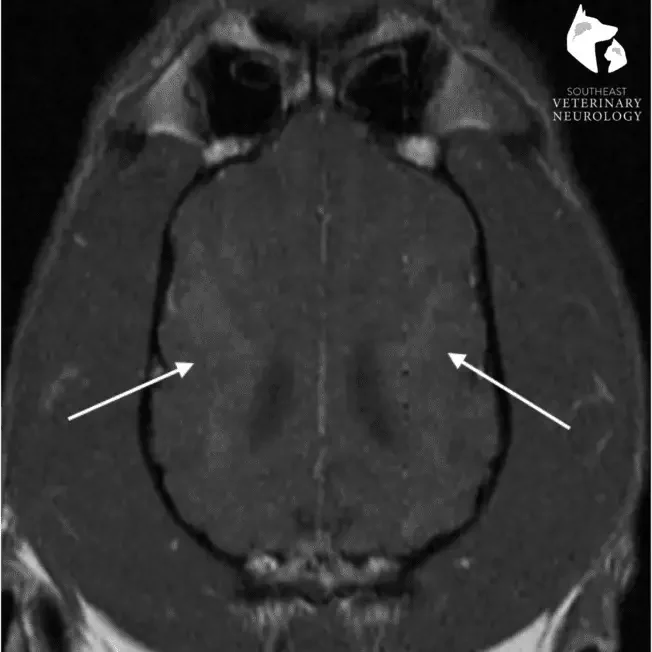

Chest radiographs and complete blood work were all normal, aside from elevated ALT (liver enzyme), which was most likely due to the smoke exposure. Finally, an MRI of Reilly’s brain revealed bilaterally symmetric contrast-enhancing lesions within the cerebral cortex and caudate nuclei, while cerebrospinal fluid analysis was normal. This was most consistent with a metabolic or toxic etiology. Therefore, the most likely cause was carbon monoxide toxicity to the brain from smoke inhalation.

Reilly MRI

MRI Of Reilly's Head